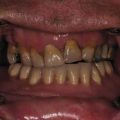

An accurate maxillofacial examination is only possible following adequate exposure, which includes cleaning the patient’s face and wound. Given the vascularity of the maxillofacial region, blood and debris from even minor soft tissue lacerations can misrepresent the severity of injury. Proper cleaning and examination of wounds may require sedation or general anesthesia to ensure patient comfort. A standard set of photographs should be obtained of patients sustaining facial trauma ( Fig. 1.18.5 ), including anterior, lateral, submental, intraoral, and wound photographs. These photos provide a baseline examination for medicolegal purposes, allow for a visual tool to describe treatment to the patient, and aid the clinician in forming the definitive treatment plan. This chapter will focus on the examination of the oral cavity and mandibular function.

Next, each remaining tooth and restoration should be evaluated systematically (see Classification section ). Transillumination of visible light along the long axis of the tooth can identify subtle dental injuries to enamel. Each tooth should be evaluated for mobility, both individually or along with its adjacent teeth (indicating a dentoalveolar fracture). Mobility of an individual tooth can indicate luxation of the entire tooth or a root fracture that can require dental radiographs to diagnose. The clinician should then evaluate the alignment of the dental arches. Teeth are most commonly displaced in a buccolingual direction due to the vector of trauma perpendicular to the tooth’s long axis. A tilting of the occlusal plane can indicate luxation or intrusion injuries, but may indicate maxillary or mandibular fracture. Each tooth should be tested for mobility in all dimensions with care not to avulse loose teeth or dentoalveolar segments. A commonly used mobility index is the Miller classification, in which tooth mobility is evaluated using two hard objects (e.g. two tongue depressors). If a tooth is nondisplaced but mobile, this may indicate either preexisting periodontal disease or a crown/root fracture. Dental fractures more coronally positioned generally have more mobility.